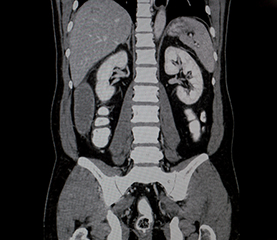

CT Abdomen si pelvis

Investigatia este utilizata pentru vizualizarea in detaliu a organelor abdominale si pelvine: rinichi, ficat, splina, pancreas, cat si pentru analizarea stomacului si a intestinelor.